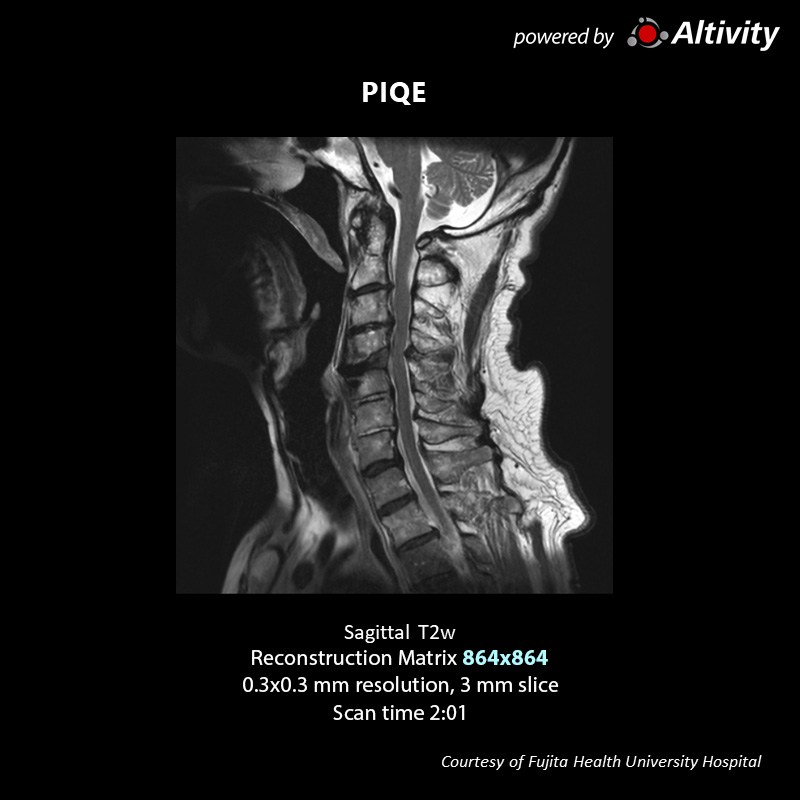

Neuro & Spine

Vantage Galan 3T

Sagittal T2w for c spin

The original image is a 288 matrix with a 3 mm slice thickness and relatively low resolution, resulting in high SNR.

PIQE reconstruction can acquire high quality images within acceptable scan times.